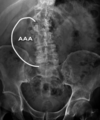

What is depicted in this AXR? [1] What does this indicate? [1]

**Abdominal aortic aneurysm - AAA** There is calcification of the dilated aortic wall Frequently only one side of the aneurysm is visible - as in this image - the other being projected over the spine